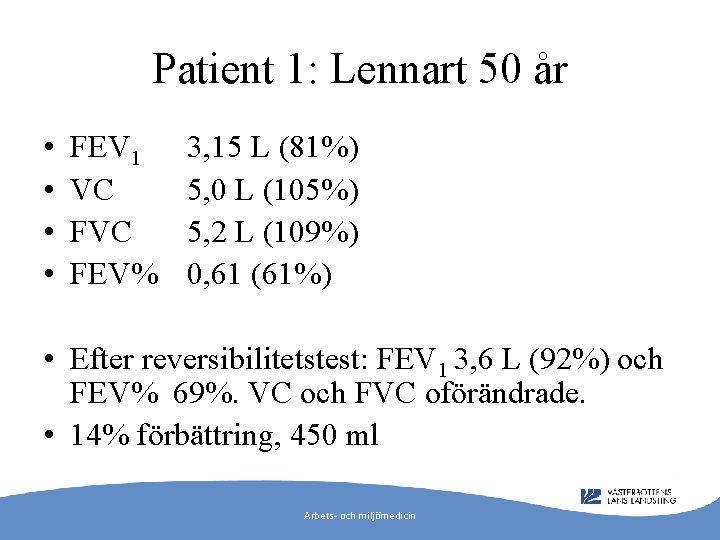

Patient 1: Lennart 50 år • • FEV 1 VC FEV% 3, 15 L (81%) 5, 0 L (105%) 5, 2 L (109%) 0, 61 (61%) • Efter reversibilitetstest: FEV 1 3, 6 L (92%) och FEV% 69%. VC och FVC oförändrade. • 14% förbättring, 450 ml Arbets- och miljömedicin

Diagnos? • Astma, men kvarstående obstruktivitet efter rev -test • Gått obehandlad länge? • Astma med KOL (pga rökning eller obehandlad astma? ) • Rökstopp, läkarbedömning Arbets- och miljömedicin